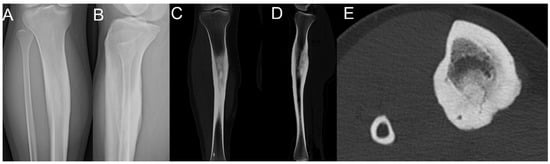

2.2. Case 2